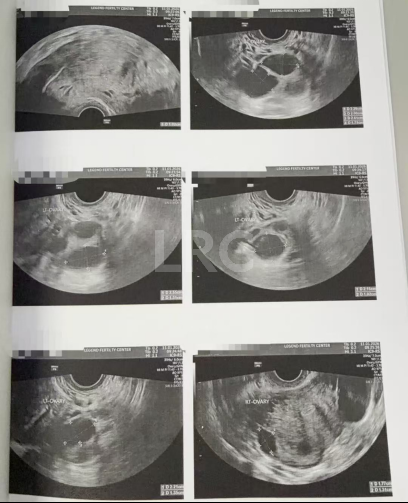

月经第二天 促排第一天

阴超检查:基础卵泡 14 颗

- 右侧卵泡 5 颗 (7,6,5,5,5mm)

- 左侧卵泡 9 颗 (7,6,6,6,6,5,5,5,5mm)

激素水平检查:

- 促黄体生成素 5.60 miu/ml

- 雌二醇 42.90 pg/ml

- 促卵泡生成素 7.60 miu/ml

- 泌乳素 9.30 miu/L

促排第六天

阴超检查(只数能用卵子):

- 右侧卵泡 6 颗 (14,11,9,9,8mm)

- 左侧卵泡 5 颗 (14,14,13,11,11mm)

- 促黄体生成素 3.60 miu/ml

- 雌二醇 313 pg/ml

促排第八天

阴超检查:

- 右侧卵泡 4 颗 (17,14,14,13mm)

- 左侧卵泡 5 颗 (17,16,16,15,15,13mm)

子宫内膜厚度:6.6 mm